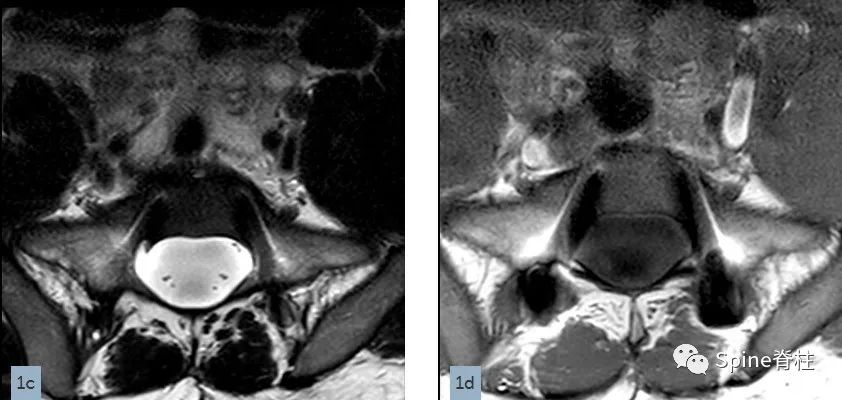

在矢状位T2(2a)和T1加权像(2b)上,多节段椎体后壁呈扇形缺损,缺少硬膜外脂肪(红色箭头),S1处的硬膜囊直径大于L4处。横断面T2(2c)和T1加权像(2d)提示硬膜囊膨胀,S1椎体后壁再次证实硬膜外脂肪缺失(红色箭头)。 其影像学表现符合硬膜扩张的诊断

硬膜扩张 (dural ectasia) 被定义为硬膜囊膨胀或增宽,常伴有神经根袖从相应椎间孔突出,有时伴有椎体后壁扇形缺损 (posterior vertebral scalloping)、椎弓根和椎板皮质变薄、神经根孔增宽或蛛网膜囊肿。但椎体后部扇形缺损也可见于正常成人,多达一半的健康成人可有轻度的椎体后部生理性扇形缺损。